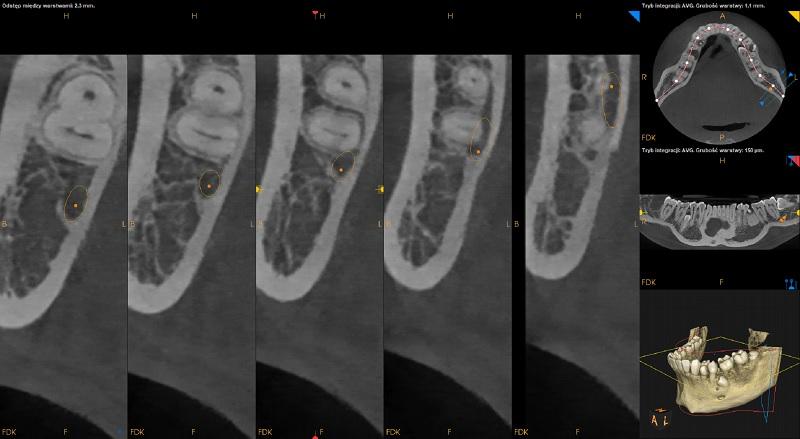

Pomiędzy korzeniami zębów 36 i 35 widoczne dwa zatrzymane zęby dodatkowe. Ząb po stronie przedsionkowej położony pionowo skośnie, koroną skierowany w stronę mezialną i policzkową. Wierzchołek korzenia w kontakcie z kanałem nerwu zębodołowego dolnego.

Ząb po stronie językowej położony skośnie, koroną skierowany w stronę mezialną. Resorpcja korzeni zębów sąsiednich niewidoczna. Pomiędzy zębami dodatkowymi ognisko zagęszczenia struktury kostnej.

Po stronie przedsionkowej zęba 34 ząb dodatkowy. Ząb 34 zrotowany w stronę dystalną. Wierzchołek korzenia dodatkowego zagięty.

Pomiędzy korzeniami zębów 34 i 33 widoczny zatrzymany mikrodontyczny ząb nadliczbowy.

Pomiędzy korzeniami zębów 44 i 45 widoczny zatrzymany ząb dodatkowy. Położony pionowo. Wierzchołek korzenia zęba zagięty. Widoczna resorpcja korzenia zęba 44.

Pomiędzy korzeniami zębów 45 i 46 widoczny zatrzymany ząb dodatkowy. Położony pionowo. Widoczna resorpcja korzenia zęba 45 oraz korzenia mezialnego zęba 46. Poszerzenie mieszka wokół korony zęba (około 3,5mm) – do obserwacji.